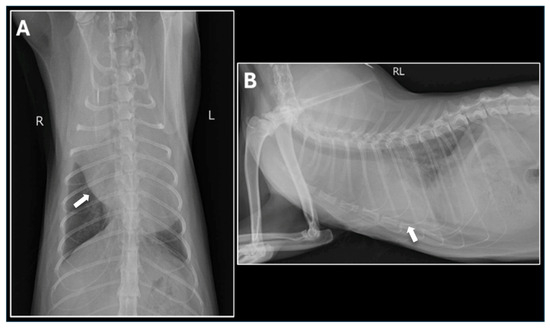

Veterinary cardiology has become a permanent fixture, both in the way of services provided by general practitioners, and also in specialized centers, which are being established in growing numbers around the world. Acquired heart disease, which develops and progresses with age, accounts for the vast majority of cardiac cases. They are also the subject of greatest interest to researchers, due to the prevalence and difficulties encountered during their treatment. Among them, the most common are myxomatous mitral valve disease in small-breed dogs, dilated cardiomyopathy in large-breed dogs and hypertrophic cardiomyopathy in cats. In contrast, congenital heart defects, which are significantly less common, can pose considerable diagnostic challenges and be cumbersome in terms of selecting the optimal treatment protocol. Due to the rapidly developing branch of interventional cardiology, including minimally invasive procedures, a growing number of defects, such as patent ductus arteriosus, pulmonic stenosis, atrial septal defects or ventricular septal defects, can be successfully addressed by surgical methods. In many cases, such treatment results in a complete recovery, which positively affects the rest of the animal's life. With the use of advanced diagnostics, such as 3D and 4D transesophageal echocardiography, cardiac magnetic resonance imaging (MRI), and cardiac computed tomography (CT), the characteristics of acquired and congenital defects and their complexities can be assessed very accurately, favoring the selection of optimal treatment methods, as well as allowing the determination of possible strategies for surgery. Thanks to this comprehensive approach, veterinary cardiology services in many countries around the world have achieved incredibly high standards of care.